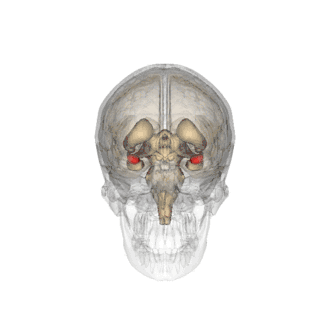

Миндалевидное тело (лат. corpus amygdaloideum), ами́гдала[1] — область мозга миндалевидной формы, находящаяся в белом веществе височной доли полушария под скорлупой, примерно на 1,5—2,0 см сзади от височного полюса. В мозге два миндалевидных тела — по одному в каждом полушарии[2]. Миндалевидное тело играет ключевую роль в формировании эмоций, в частности, страха. У пациента, миндалевидное тело которого оказалось полностью разрушено вследствие болезни Урбаха — Вите, наблюдалось отсутствие страха[3][4][5]. Миндалевидное тело также играет важную роль в функционировании памяти, принятии решений и эмоциональных реакциях[6]. Миндалевидное тело является частью лимбической системы, относится к подкорковым обонятельным центрам.